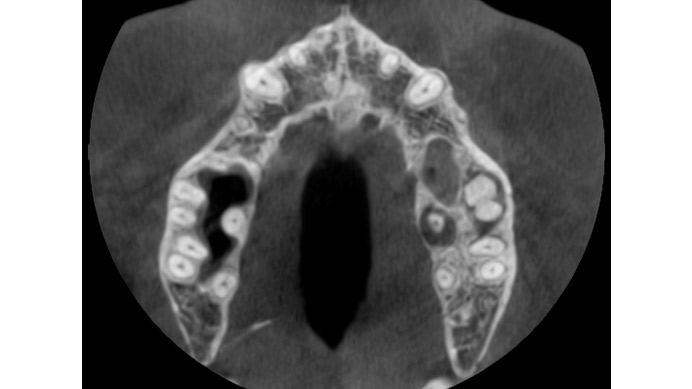

Ian es un paciente que nos cuenta su experiencia tras una intervención de cirugía periapical. Ian vino a la clínica dental IDIM con molestias en una muela superior que en el estudio radiográfico se vio que presentaba infección a causa del fracaso de una endodoncia.

Se decidió realizar una cirugía periapical para eliminar la infección y sellar las raíces con un empaste para evitar que volviera a tener problemas. Gracias a esta efectiva intervención Ian conserva su muela, lo cual es preferible, siempre que se puede, a tener que extraerla y sustituirla con un implante dental.